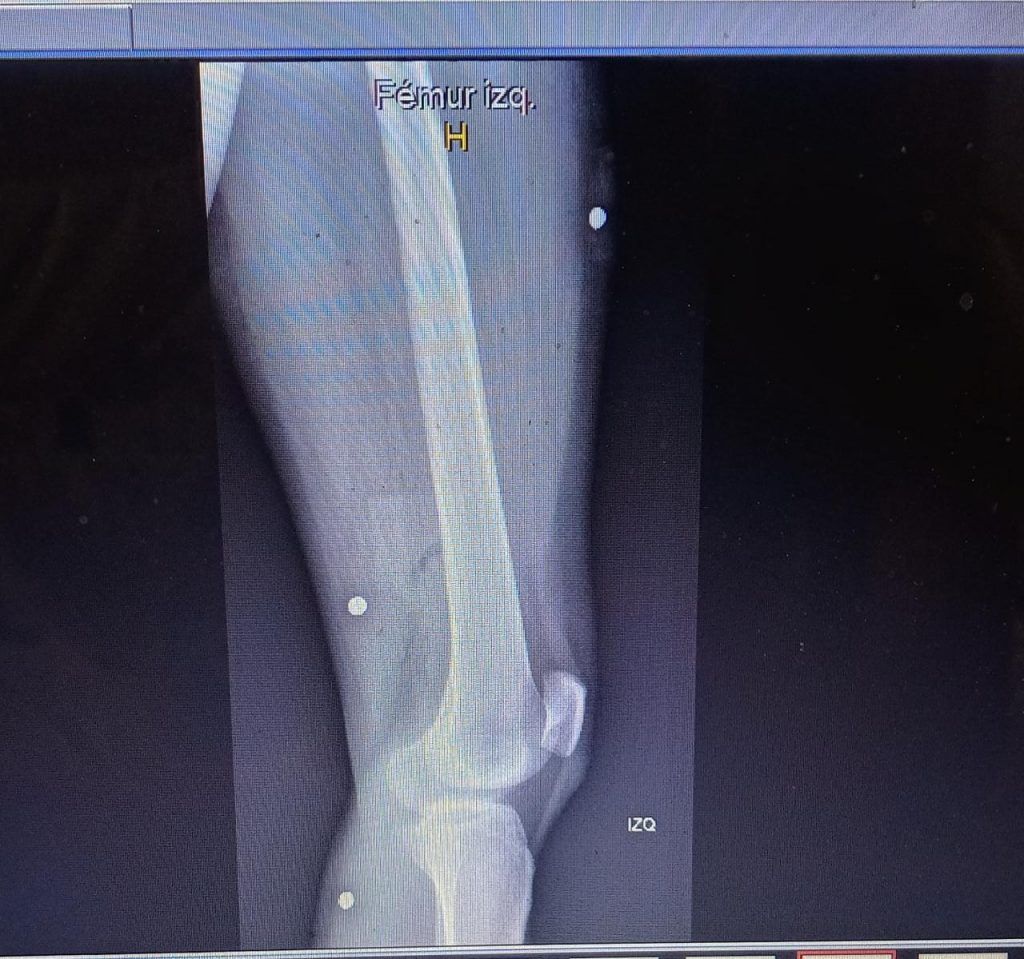

Otra tarde de viernes, la del 13 de diciembre, fue, también, traumática para Carolina, quien habla con identidad reservada. A las 20 horas terminó su jornada laboral en las calles del centro, donde la empresa la había destinado para vender servicios de telecomunicaciones. La joven, sanmiguelina y de 31 años, iba por la Alameda, en busca de locomoción para devolverse a su casa, cuando sintió que se le “entumecía” la pierna izquierda. Acababa de recibir seis balines, cuatro de ellos le penetraron la carne hasta adentro. Un tipo la tomó en brazos y la sacó de la multitud.

[caption id="attachment_408346" align="alignnone" width="1024"]perdigones Radiografía de la pierna de Carolina / Foto cedida[/caption]